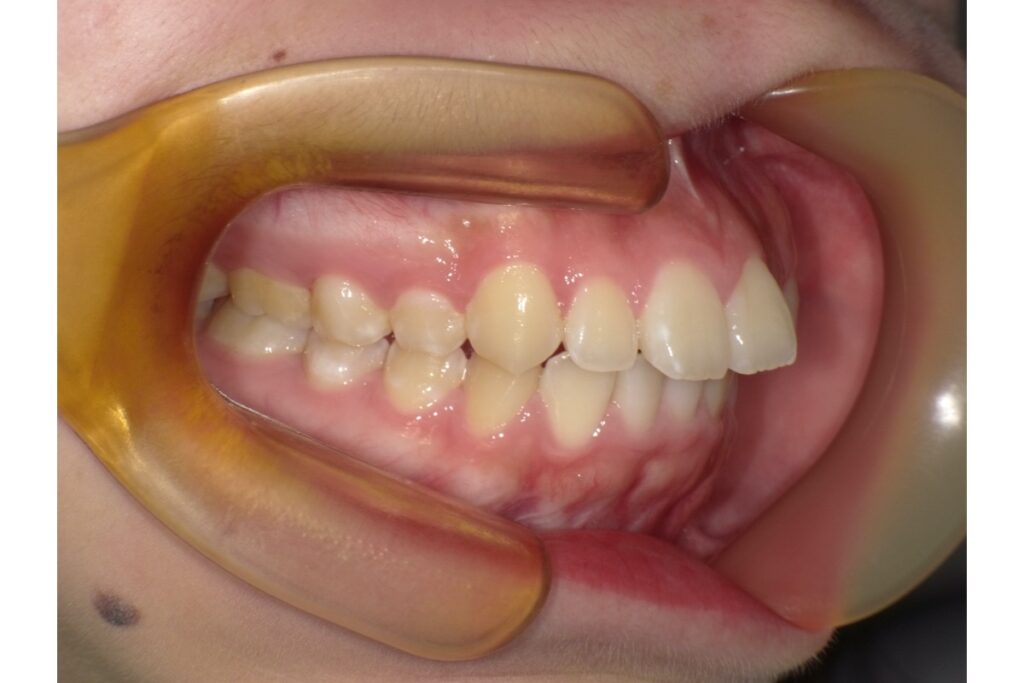

ゴボ口の方に多いのは、歯が顎の骨より外に並んでしまっている「上下顎前突」や「唇側傾斜」と呼ばれる状態です。このようなケースでは、第一小臼歯などを抜歯し、そのスペースを利用して前歯を後ろに下げる「抜歯矯正」がよく行われます。